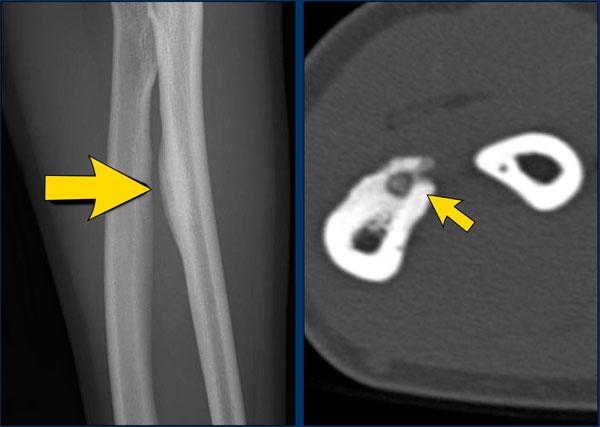

On the left three bone lesions with a narrow zone of transition.

Based on the morphology and the age of the patients, these lesions are benign.

Notice that in all three patients, the growth plates have not yet closed.

Images

1. Non-ossifying fibroma

2. Solitary bone cyst

3. Aneurysmal bone cyst